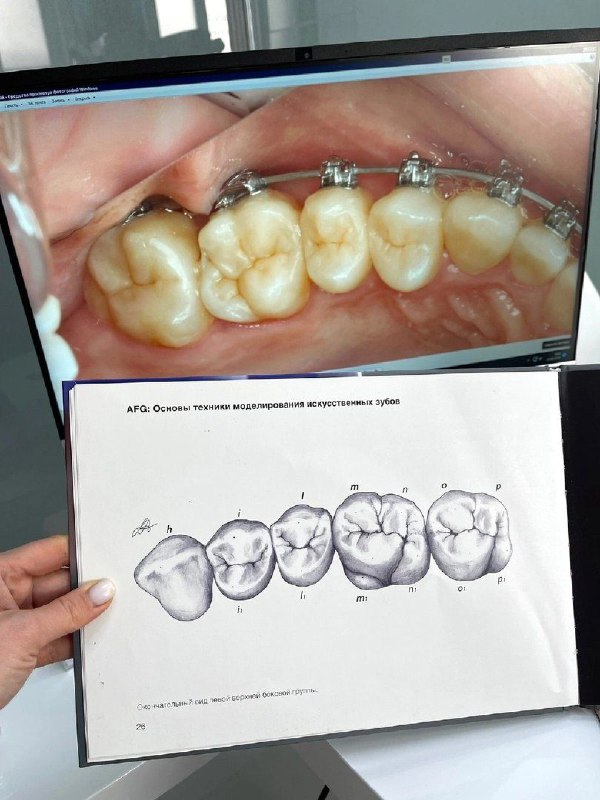

✨Рекол 1,2 месяца уже на брекетах. Билдапы длительного ношения. Это последний сегмент одного и того же пациента из рубрики как с картинки. Готовились к ортодонтии. Поэтому показания были расширены и в

28 февр. 2026 г.

3.5k 29 10